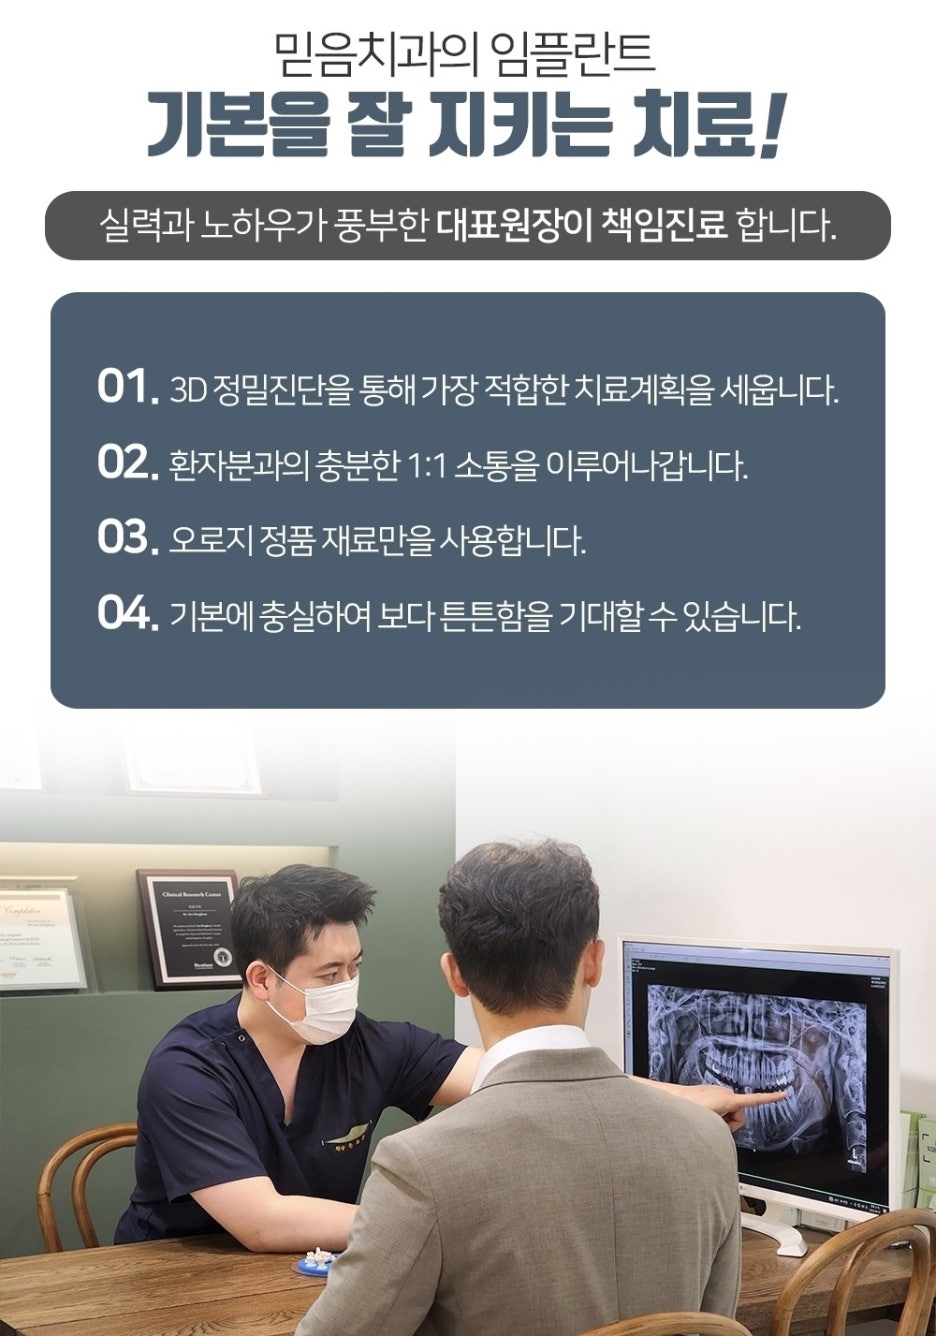

사진을 보시면, 해당 환자분은 임플란트 식립만 해둔 채 보철을 연결하지 않은 상태로 약 2년이 지난 뒤 내원하셨습니다.

오랜 기간 치아가 없는 채로 지내시다 보니, 아래 사진처럼 비어 있던 자리 안쪽으로 볼 조직이 들어와 공간을 메우고 있는 모습을 확인할 수 있었습니다.